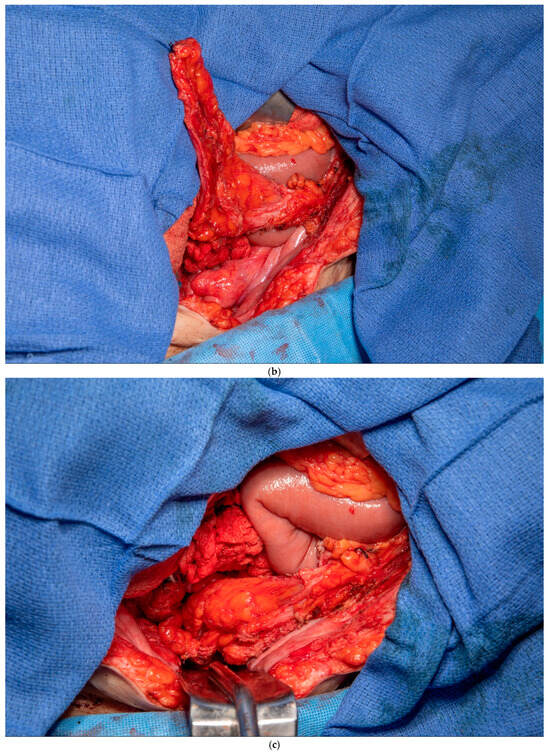

3.2. Peritoneal, Preperitoneal Fat and Falciform Ligament Flap

This patient had no greater omentum left, as it was removed during a previous total abdominal colectomy. A VRAM was also not possible because she had bilateral rectus abdominus divisions from transverse incisions as a child, and no perforators to the skin could be identified. However, she had some remaining deep perforating branches of the inferior epigastric artery. She required a proctectomy because of a rectovaginal fistula and anal stenosis. Once the midline laparotomy incision was made with the assistance of a plastic surgeon, the peritoneum and preperitoneal fat were dissected off her posterior sheath bilaterally (See Figure 3a,b). The falciform ligament was ligated, divided as high as possible, and kept in continuity with the peritoneum and peritoneal fat flap. A persistent branch of the deep inferior epigastric vessel supplying this tissue was identified and protected. The peritoneum was also mobilized off the lower aspect of the rectus muscle to allow the flap to be advanced toward the pelvis. Doppler ultrasonography was used to confirm that blood supply to the flap was maintained. The flap was then secured to the pelvic inlet in a sling-like fashion to keep the small intestine out of the pelvis (See Figure 3c). A 19 Fr drain was placed in the pelvis at the end of the case.

Figure 3.

(a) Peritoneum and preperitoneal fat dissected off the patient’s left posterior sheath. (Used with permission from the Mayo Foundation for Medical Education and Research; all rights reserved). (b) Peritoneum, preperitoneal fat, and falciform ligament dissected off the patient’s right posterior sheath. (Used with permission from the Mayo Foundation for Medical Education and Research; all rights reserved). (c) Bilateral pedicled flaps sutured to the pelvic inlet, creating a sling to prevent a small bowel from falling into the pelvis. (Used with permission from the Mayo Foundation for Medical Education and Research; all rights reserved).